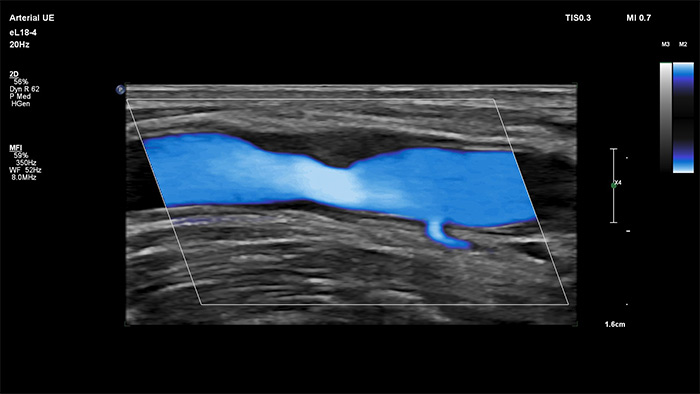

MicroFlow Imaging de Philips est conçu pour détecter les flux de très faible vitesse et de petit calibre au sein des tissus, avec une sensibilité remarquable, et améliore la résolution du flux lors d’explorations vasculaires. Grâce à sa haute résolution et à son faible nombre d’artefacts, les cliniciens peuvent visualiser et caractériser des perturbations subtiles du débit autour d’une plaque sténosée afin d’établir des diagnostics fiables.